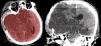

Intracranial volume (ICV) is an important tool in the management of patients undergoing decompressive craniectomy (DC) surgery. The aim of this study was to validate ICV measurement applying the shape-based interpolation (SBI) method using open source software on computed tomography (CT) images.

MethodsThe pre- and post-operative CT images of 55 patients undergoing DC surgery were analyzed. The ICV was measured by segmenting every slice of the CT images, and compared with estimated ICV calculated using the 1-in-10 sampling strategy and processed using the SBI method. An independent t test was conducted to compare the ICV measurements between the two different methods. The calculation using this method was repeated three times for reliability analysis using the intraclass correlations coefficient (ICC). The Bland–Altman plot was used to measure agreement between the methods for both pre- and post-operative ICV measurements.

ResultsThe mean ICV (±SD) were 1341.1±122.1ml (manual) and 1344.11±122.6ml (SBI) for the preoperative CT data. The mean ICV (±SD) were 1396.4±132.4ml (manual) and 1400.53±132.1ml (SBI) for the post-operative CT data. No significant difference was found in ICV measurements using the manual and the SBI methods (p=.983 for pre-op, and p=.960 for post-op). The intrarater ICC showed a significant correlation; ICC=1.00. The Bland–Altman plot showed good agreement between the manual and the SBI method.

ConclusionThe shape-based interpolation method with 1-in-10 sampling strategy gave comparable results in estimating ICV compared to manual segmentation. Thus, this method could be used in clinical settings for rapid, reliable and repeatable ICV estimations.